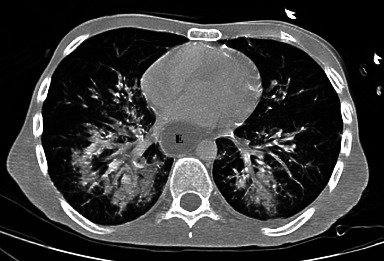

肠系膜上动脉综合征(SMAS)是一种罕见的不寻常疾病,经临床怀疑和放射学证实。由于腹腔内脂肪减少,十二指肠第三部分与腹主动脉(AA)和肠系膜上动脉(SMA)之间发生撞击,继发十二指肠梗阻。高发病率和高死亡率与漏诊或晚诊有关,而漏诊或晚诊可导致胃穿孔和胃出血等并发症。我们介绍了一例 33 岁的男性病例,他以前并不知道自己患有 SMAS,因出现脓毒性休克症状而到急诊科就诊,主诉发烧和呼吸道症状持续数天。检查结果显示,吸入性肺炎继发于上消化道梗阻,计算机断层扫描(CT)显示有 SMAS 征象。病情急剧恶化导致心脏骤停并死亡。通过这篇文章,我们强调了早期正确诊断 SMAS 的重要性,因为没有一个数字是严格意义上的诊断,必须根据临床病史和体格检查来解释放射图像,所以诊断 SMAS 有时很困难。

Superior mesenteric artery syndrome (SMAS) is a rare and unusual disease, suspected clinically and confirmed radiologically. It represents a duodenal obstruction secondary to the impingement of the third portion of the duodenum between the abdominal aorta (AA) and the superior mesenteric artery (SMA) due to decreased intraabdominal fat. High morbidity and mortality rates are linked to missed or late diagnosis that can lead to complications, such as gastric perforation and gastric hemorrhage. We present the case of a 33-year-old man who was not previously known to have a SMAS, who presented to the emergency department with signs of septic shock, complaining of fever and respiratory symptoms for several days. Investigations showed aspiration pneumonia secondary to an upper gastrointestinal obstruction with signs of SMAS on a computed tomography (CT) scanner. Acute and rapid deterioration led to cardiac arrest and death. Through this article, we highlight the importance of early and correct diagnosis of SMAS which can sometimes be challenging, since no number is strictly diagnostic and radiological images must be interpreted in light of the clinical history and physical examination.